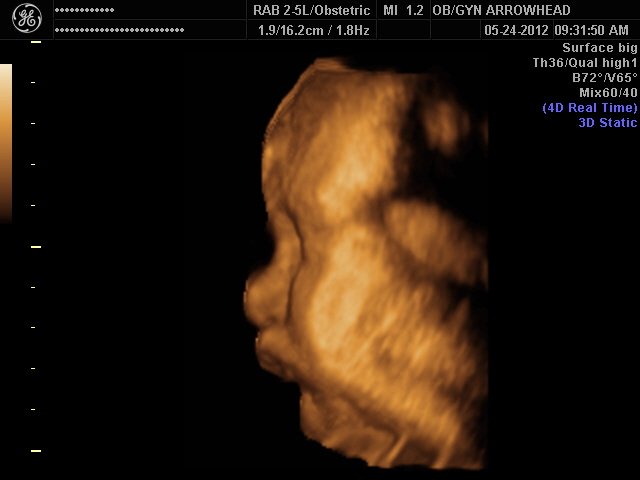

We offer complimentary 3D/4D Ultrasounds to all our OB patients around 30 weeks! The following photos are some examples of our work, shown with permission from our patients.